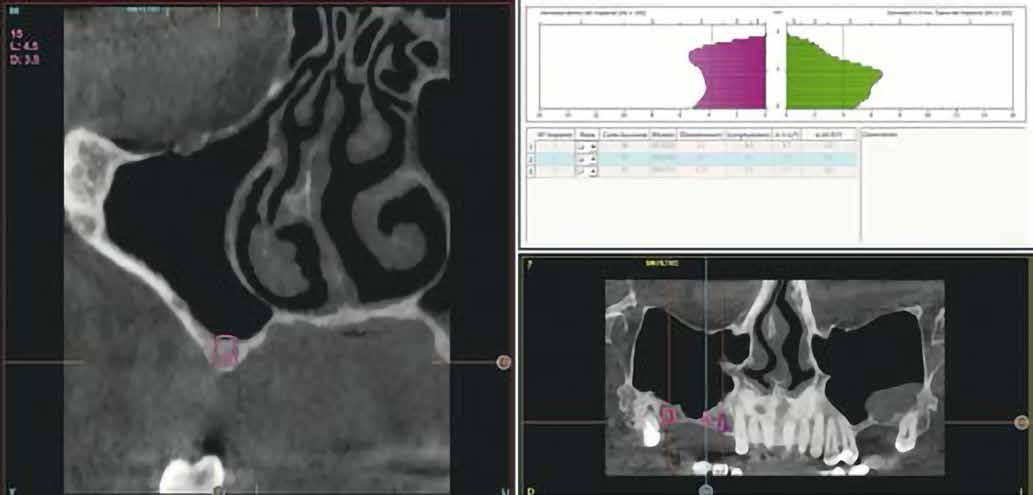

és jelentős mobilitással rendelkezett. A radiológiai vizsgálat után egyértelműen látszódott, hogy a fogon még nem végeztek gyökérkezelést. A 2.6-os és 2.7-es fogaknak megfelelő területen az arcüreg kiterjedése jelentős volt, vertikális csontmennyiség szignifikánsan csökkent (1. és 2. ábra).

1. ábra: Megfelelő szájhigiénia – panorámaröntgen. 2. ábra: A 2.5, 2.6 és 2.7-nek megfelelő terület a röntgenfelvételen.

Az alábbi esetnél egy olyan pácienst szeretnénk bemutatni, akinél a csontmennyiség nem volt megfelelő a maxilla hátsó részén, ennek következtében a kezelést rövid implantátummal, továbbá a tuber területére behelyezett ferde implantátummal végeztük. Ez egy pácienscentrikus alternatív kezelési eljárás, annak érdekében, hogy az arcüregemelés elkerülhető legyen.

Esetbemutatás

Kiindulási szituáció Egy 49 éves, nem dohányzó, egészséges férfi páciens jelentkezett a rendelőnkben hiányzó 2.6-os és 2.7-es foggal, valamint azzal a panasszal, hogy már lassan egy hete, lüktető fájdalmat érez a 2.5-ös fogánál. Megoldást keresett a hiányzó fogak pótlására is. Klinikai intraorális vizsgálat alapján a 2.5-ös fogon egy sérült fémkerámia korona volt,